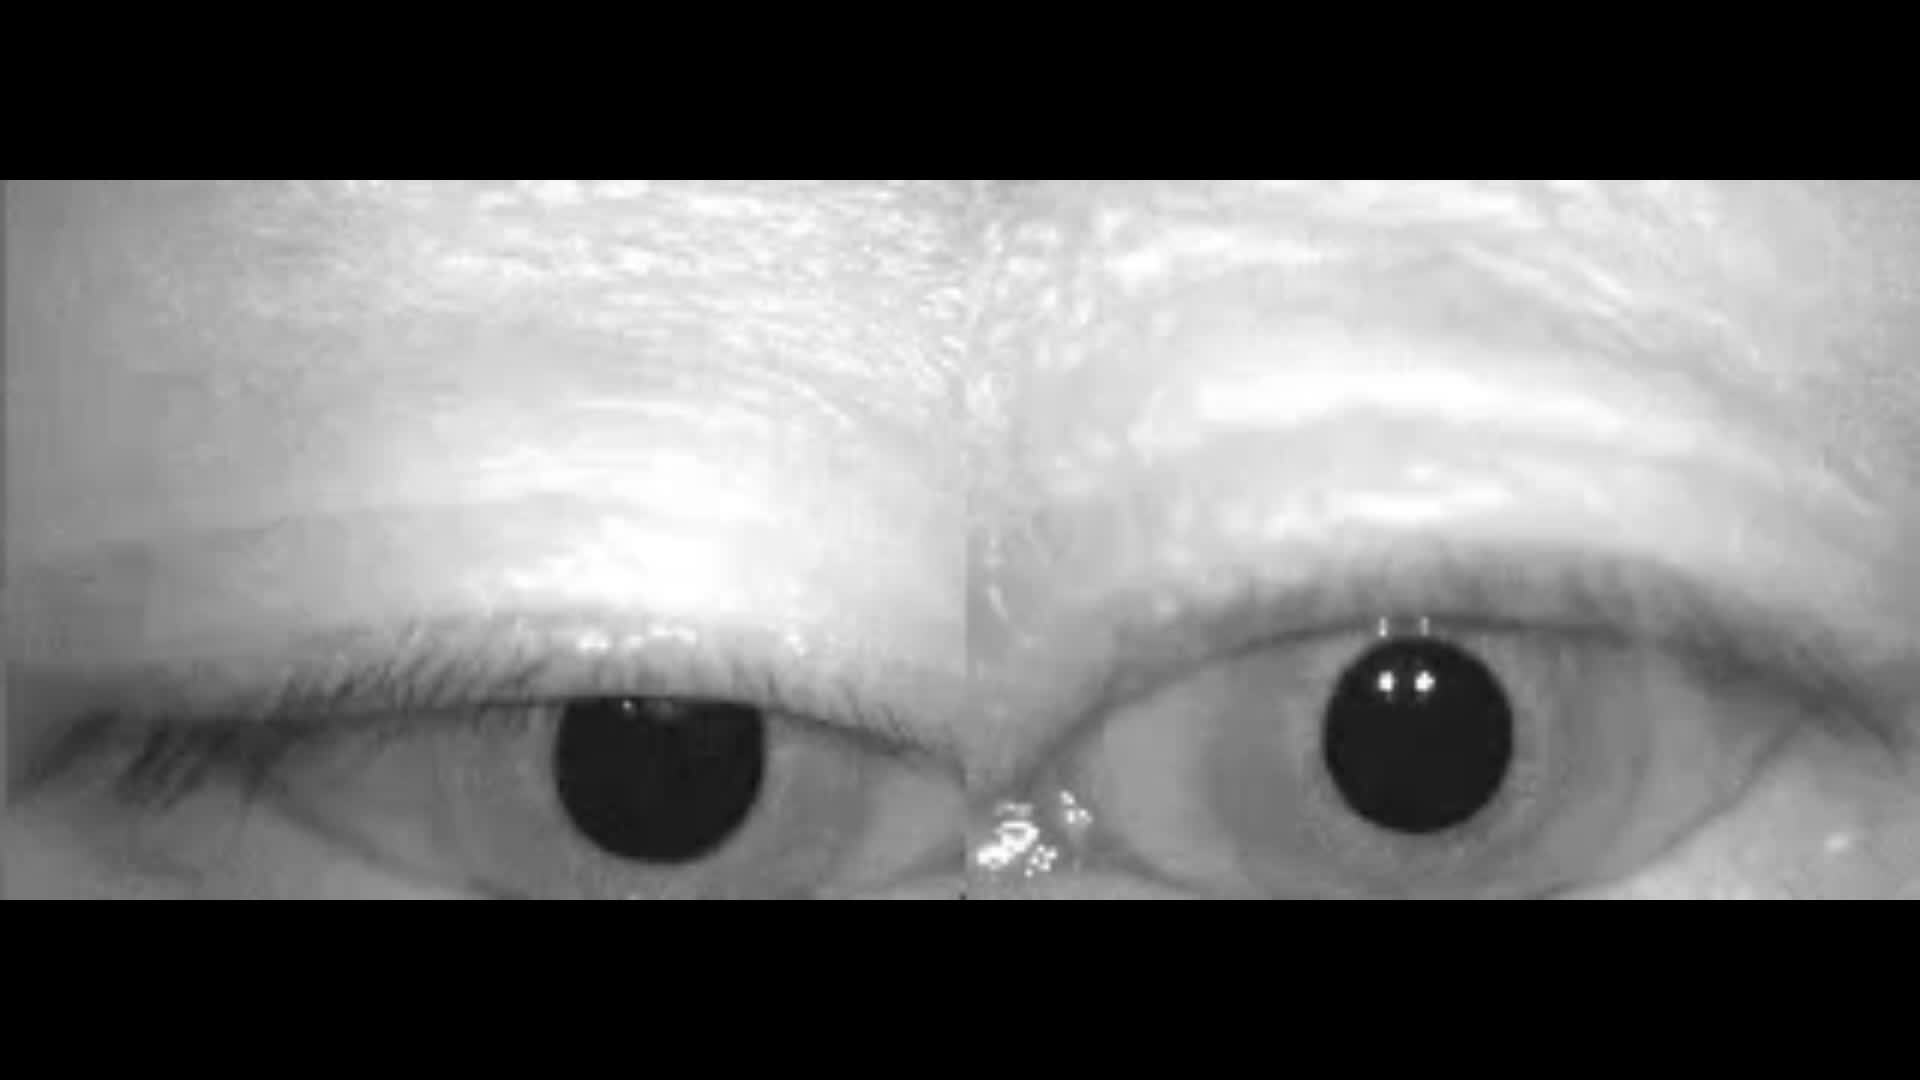

上半规管耳石症非常罕见,患者表现为坐卧位改变时出现下跳性眼震,如下面视频。